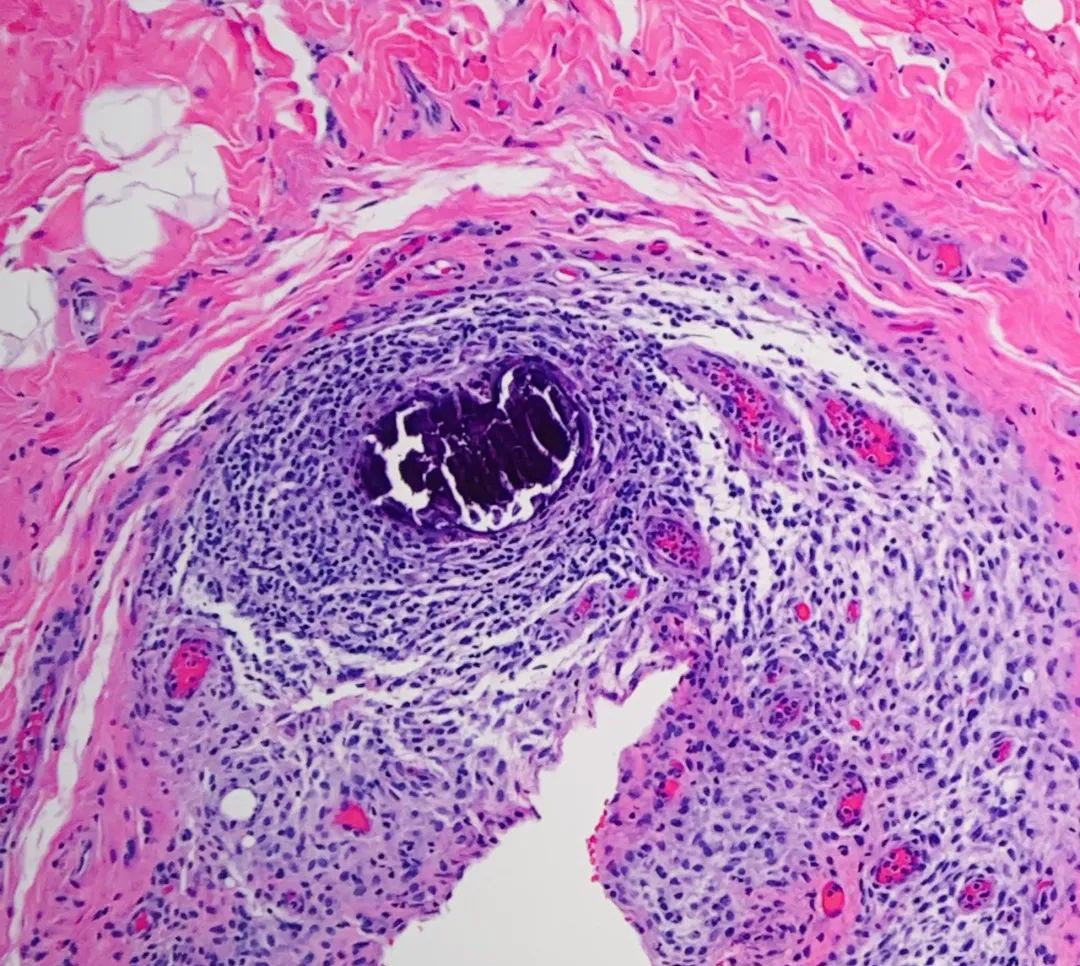

MTC源自甲状腺C细胞,诊断时超过70%的患者已出现淋巴转移,约10%伴随远处转移,治疗难度高、复发率高,预后相对较差其治疗瓶颈主要包括: